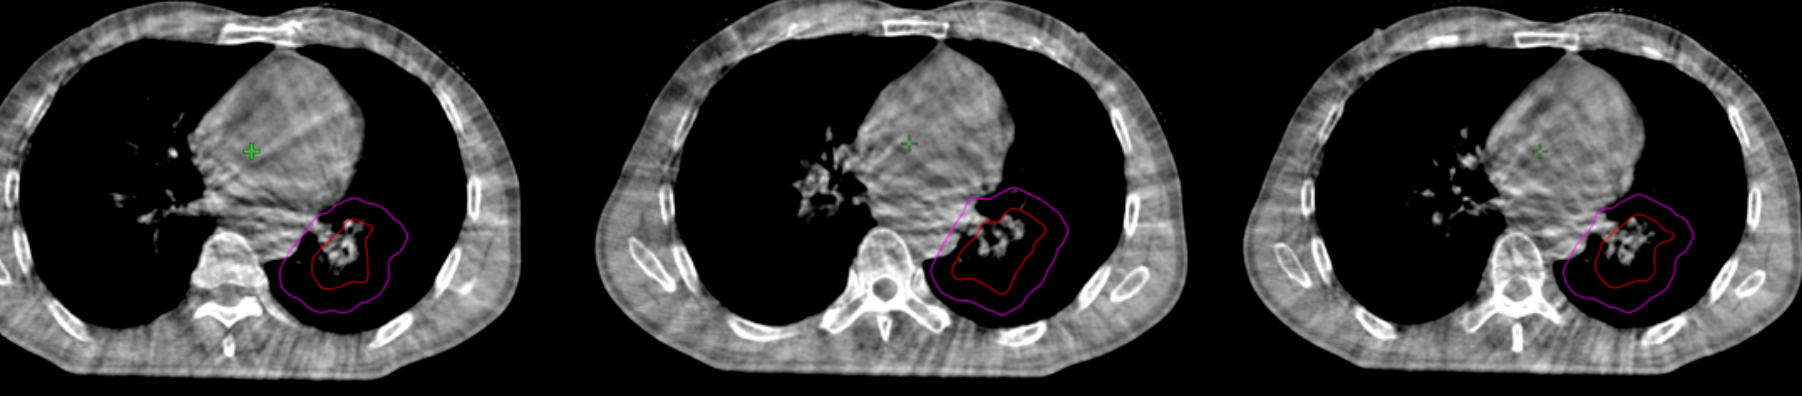

(▲患者最后一次放疗CBCT影像图(放疗后))

经过一个疗程的放射治疗后,最后一次放疗CBCT(下图)显示患者左肺门的肿块明显缩小,肿瘤对支气管的压迫得到有效解除。其咳嗽、咯血的症状基本消失,生活质量获得显著提升。